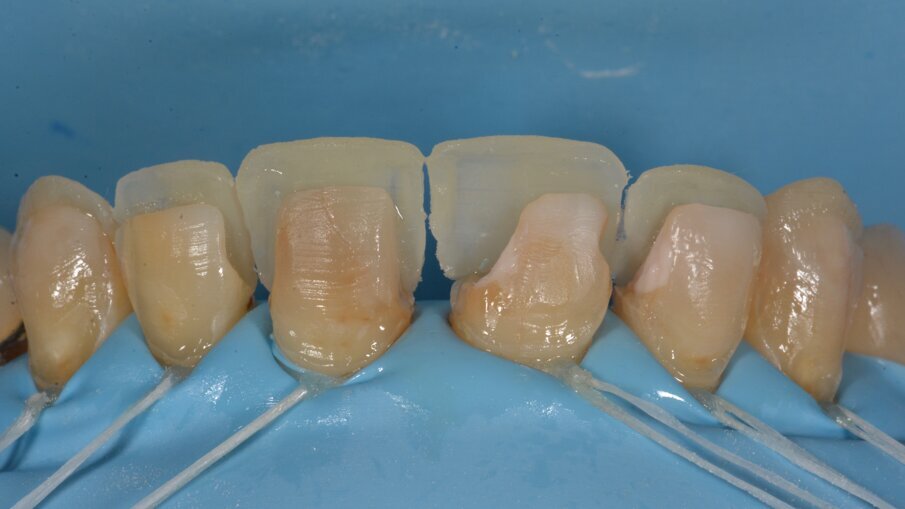

Het intermediair resultaat na opvullen van de buccale vlakken. Voor het afwerken en polijsten werd gebruik gemaakt van het Essential Shape protocol ontworpen door Style Italiano.

Zodra de primaire anatomie is aangebracht kunnen we de secundaire anatomie aanbrengen in de vorm van oppervlakkige mamelons. Deze worden ook eerst aangebracht met potlood en dan ingekerfd met een traag draaiende diamantboor.